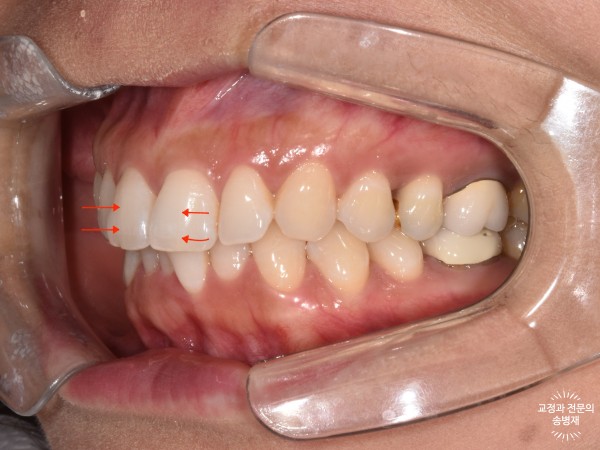

위에서 빨간 화살표로 표시한 실금이 잘 보이시나요?

치아에서 보이는 실금은 craze line이라고 부르며, 치아 표면 약 0.1mm 내의 야주 얕은 깊이의 실금입니다.

이러한 실금은 훨씬 더 깊이 금이 간 치아파절(crack line)과 구별됩니다.